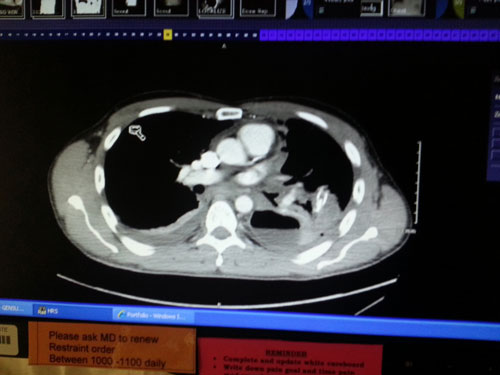

After 4 hours in the emergency room the doctor finally ordered a CT scan and they discovered it wasn’t pneumonia. His chest was full of fluid compressing one of his lungs more and more with every breath. They immediately popped him like a juice box and installed a chest drain to get the fluid out. Over a liter of fluid drained in the first hour. The doctors still didn’t know exactly what was wrong with Mike though. It was first diagnosed as pneumonia, then chest trauma due to roller derby before it was finally correctly diagnosed as Boerhaaves Syndrome.

Latest update on Handsome…when I showed up to the hospital this morning he was taking a walk with the nurse. That was great to see! They have been taking chest xrays every day and the fluid is finally clearing. The draining has significantly decreased. They did 2 ct scans yesterday evening. Doc said today now the feel he got food poisoning and tore a hole in his lower esophagus which leaked fluids causing inflammation and infection. They have him on antibiotics and pain meds that make him hallucinate. He cant have food or water, just iv. The ct scan shows no apparent hole so they feel it is healing on its own so no surgery at this time. He will be in hospital a few more days. They cant release him until no more fluids draining and his pain is under control.